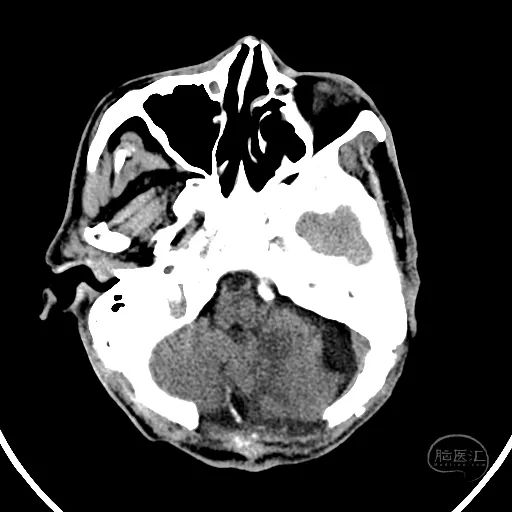

颅脑CT可见左侧小脑半球挫裂伤,第四脑室明显受压。

右额叶脑挫裂伤并血肿,侧脑室额角受压,脑室无明显扩张。

中线结构稍向左侧偏移。

骨窗显示枕骨粉碎性骨折,累及枕骨大孔左侧,齿突尚居中。